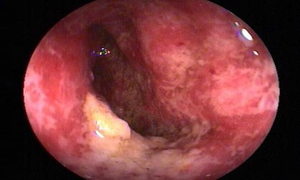

粪便常规、血常规检查。大便培养出致病菌是确诊的关键。必要时可行X线钡剂,结肠镜检查,有助于鉴别诊断。

痢疾,中医病证名。是以大便次数增多,腹痛,里急后重,痢下赤白黏冻为症状。是夏秋季节常见的传染病。主要病因是外感时邪疫毒和饮食不洁两方面。病机主要为邪蕴肠腑,气血壅滞,传导失司,脂络受伤而成痢。病位在肠,与脾胃有密切关系。痢疾的治疗应根据其病证的寒热虚实而定。西医学中的细菌性痢疾、阿米巴痢疾为主,而临床上溃疡性结肠炎、放射性结肠炎、细菌性食物中毒等出现类似本节所述痢疾的症状者,均可参照辨证处理。